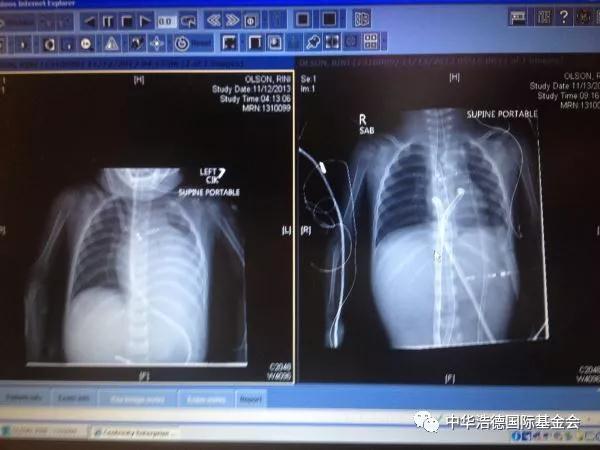

玲玲在美国的治疗也是十分艰辛,当飞机降落在美国时,玲玲就直接被送入Doernbecher儿童医院。那里心脏病科医生和护理人员告诉我们,她的心脏病到了末期,做不了手术。但是家庭都深信她离开这个世界的时间还没有到,他们不住地为她祈祷,在接下来的4周,永玲的心脏每况愈下,家庭给她的手掌和脚掌做了灰泥的印记,还请了摄影师到医院给她们家拍了一张家庭合照。这样一直到10月16日,西雅图儿童医院同意评估玲玲的心脏移植手术。她的妈妈和她搭乘救护直升飞机,到了心脏ICU。事情进展迅速,她因呼吸衰竭而接受插管治疗的当天就接纳为高危心脏移植候选人。在美国等待一个可移植的儿科心脏平均要3到5个月的时间。她上了移植名单的8天后,她第一次心搏停止,继而被接上体外膜氧合生命维持器,估计只能活3到4周。随着一天一天过去,她接连患上各种并发症。但是在11月12日星期二,也就是她上了移植手术名单的19天后,西雅图儿童医院移植医生Mike McMullen进入玲玲的房间,告诉家庭说:“有一个适合玲玲的心脏了”。当移植科医生集中在美国的某间医院,在那里一个家庭的孩子去世了,他们在悲痛中所做的选择是把玲玲从死亡的边缘中救了回来。玲玲当天晚上9点半进入手术室。家庭从心脏重症监护室的窗口看到救护车把捐给玲玲的心脏送来了。这颗心经过了两千英里的飞行终于到达目的地。当治疗小组把玲玲的治疗由体外膜氧合生命维持器转换到接受体外循环时,她的心搏刚好停止了。这是医生后来告诉家庭的。很快地,另一个家庭的宝贵孩子的心被安装在新的家,就像一个收养孩子到了新家一样。不是失去,而是希望。